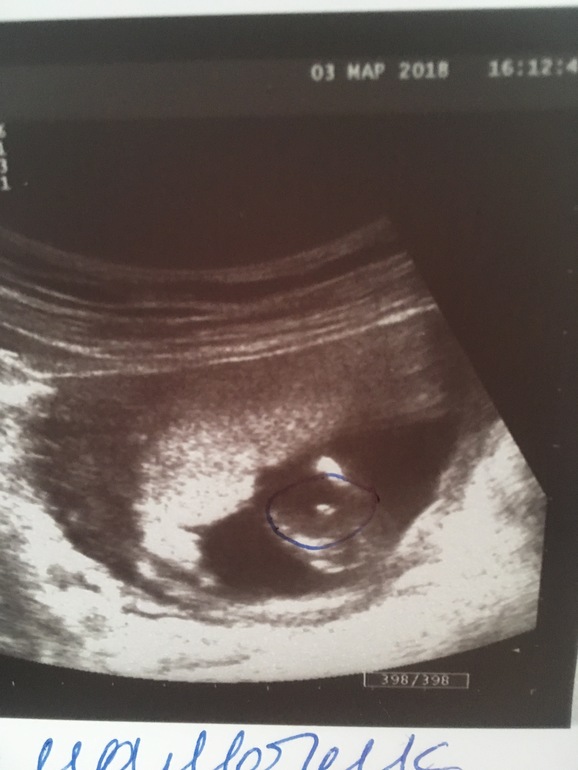

Девушки, вопрос может и глупый) ходили на УЗИ, 17-ая неделя, сказали девочка, но я Фома не верующая, просто думала что снова мальчик будет с сыном на этом же сроке сказали пол. Вопрос в том, похоже Вам на девочку?) заранее спасибо за ответы.

Девочка точно!!У меня два пацана и на узи в таком положении отчетливо видно было выпирающий пенис и мошонку у обоих.А тут кофейное зернышко - точно!!

Блин, вроде у меня столько девчонок, но вот таких «пирожков» я не видела) По-мне, так на девочку не особо похож, или у моих слишком узенькие полосочки были))) Я за мальчика, наверно)

Варианта всего 2. На фото вообще ничего не понятно. Как по таким фоткам на оруме могут рассмотреть лучше узиста - мне тоже не понятно)))